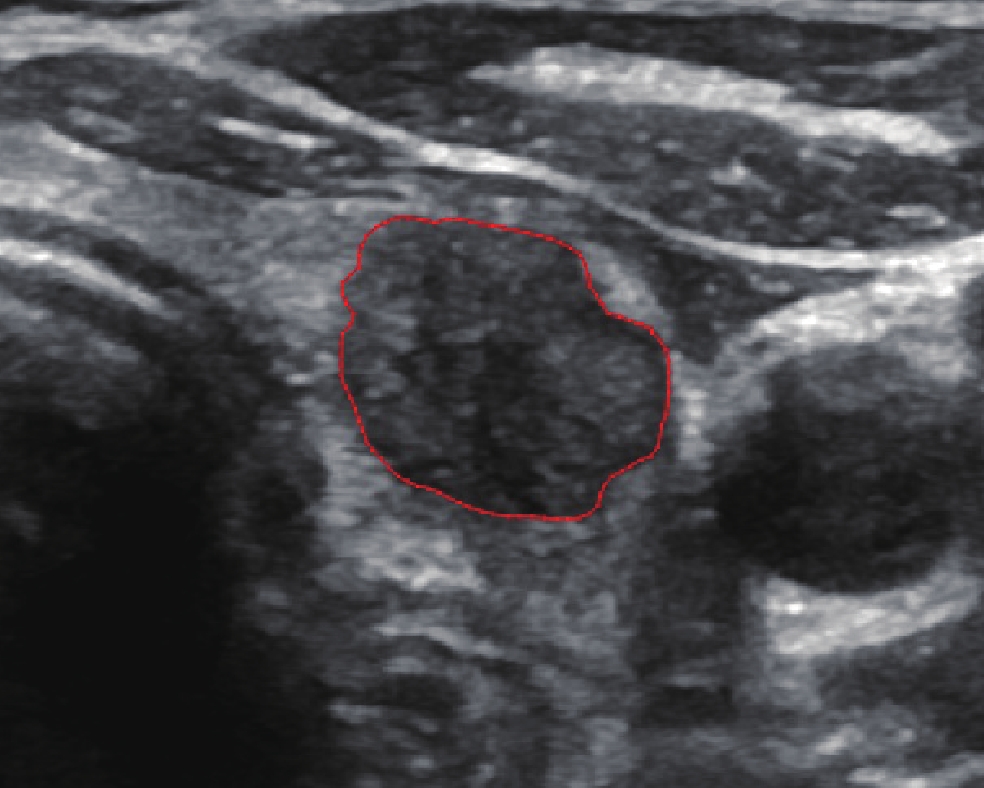

将PTC图像导入一款免费开源的影像图像分析软件ITK-Snap[18](版本3.4.0,http://www.itksnap.org/)。由一名超声科医师(5年超声诊断经验)手动分割PTC感兴趣区(Region of interest, ROI),分割完成后由另外一名超声科医师(6年超声诊断经验)修正上述ROI用于后续分析,见图1。进一步在uAI Research Portal平台(联影智能,中国上海)中提取PTC影像组学特征,包括7类特征:一阶特征、形状、灰度共生矩阵、灰度行程矩阵、灰度大小区域矩阵、灰度相关矩阵及邻域灰度差矩阵,以上影像组学特征符合《图像生物标志物标准化倡议》[19]。